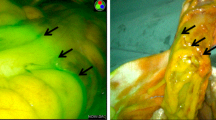

In the improved low ligation group, the lymph nodes with adipose tissue from the root of the IMA to the bifurcation of the superior rectal artery (SRA) and the LCA were carefully dissected and the artery wall was clearly exposed. Then, the LCA was dissected from its origin to the left until the inferior mesenteric vein (IMV) was recognized. The extraction of lymph nodes was continued along the IMV up to the same level of the origin of the IMA. Subsequently, the IMV was ligated at the level of the root of the IMA, and the IMA was ligated below the LCA, with preservation of the LCA. Therefore, the adipose tissues with lymph nodes in the area surrounded by the IMV, IMA and LCA were removed entirely (Fig. 2A).

Surgical image of improved low ligation and high ligation of the inferior mesenteric artery. (A) Improved low ligation, the dashed line indicates the ligation site of the SRA; (B) high ligation, the dashed line indicates the ligation site of the root of the IMA. IMA inferior mesenteric artery; IMV inferior mesenteric vein; LCA left colic artery; SRA superior rectal artery.

In the high ligation group, the lymph nodes and adipose tissues around the root of the IMA were completely dissected. Subsequently, the root of the IMA was cut 1 cm from the abdominal aorta. Then, the IMV was found and ligated at the same level (Fig. 2B).